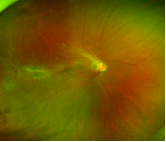

目前FEVR的診斷主要通過其臨床特點(diǎn)、眼底熒光素造影(FFA)、致病基因檢測等途徑。FFA檢查能發(fā)現(xiàn)早期無癥狀者,可明確病變范圍和預(yù)示病情發(fā)展,指導(dǎo)治療。因此一旦確診FEVR,其近親屬即使沒有任何臨床癥狀也建議行FFA檢查。廣角眼底照相技術(shù)具有無創(chuàng)、快速便捷等特點(diǎn), 可應(yīng)用于FEVR患者的快速篩檢和診斷。患者病變程度不同,治療方法各異,主要包括:視網(wǎng)膜激光光凝術(shù)、鞏膜外墊壓術(shù)、玻璃體切割術(shù)及抗-VEGF藥物的輔助治療。

造影 廣角眼底照相